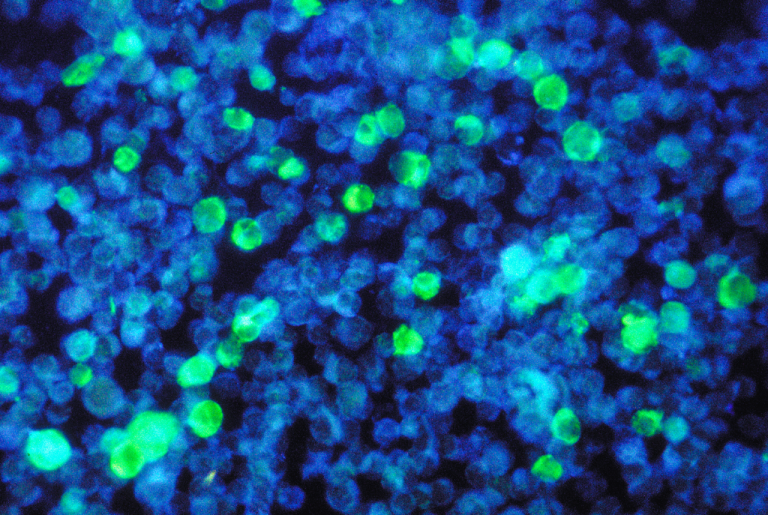

· New mechanistic study in Science Translational Medicine identifies Epstein-Barr virus as a potential trigger of the autoimmune disease systemic #lupus erythematosus